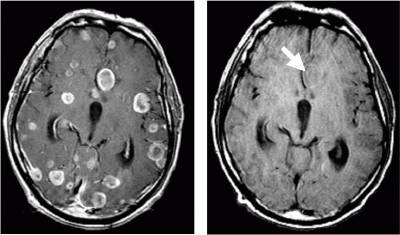

«Золотой стандарт» в диагностике метастатического рака головного мозга — магнитно-резонансная томография (МРТ). Во время этого исследования получают изображения внутренних структур тела, используя сильное магнитное поле. По снимкам врач может судить о количестве, размерах, расположении метастатических очагов.

- МРТ ‒ золотой стандарт диагностики прогрессивных раковых опухолей в этих областях. В зависимости от вида вторжения, изменяется качество изображения.